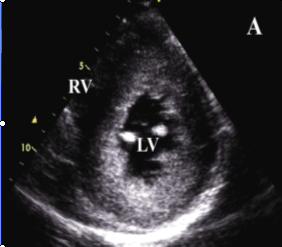

原發性心肌病1.擴張型心肌病

早期即可見心腔輕度擴大,尤其是左心室,室壁運動減弱,後期各心腔均擴大,室間隔及左室後壁運動也減弱,二尖瓣前葉雙峰可消失,而前後葉呈異向活動,左心室噴血指數常減至50%以下,心肌縮短比數也減小,可有少量心包積液。